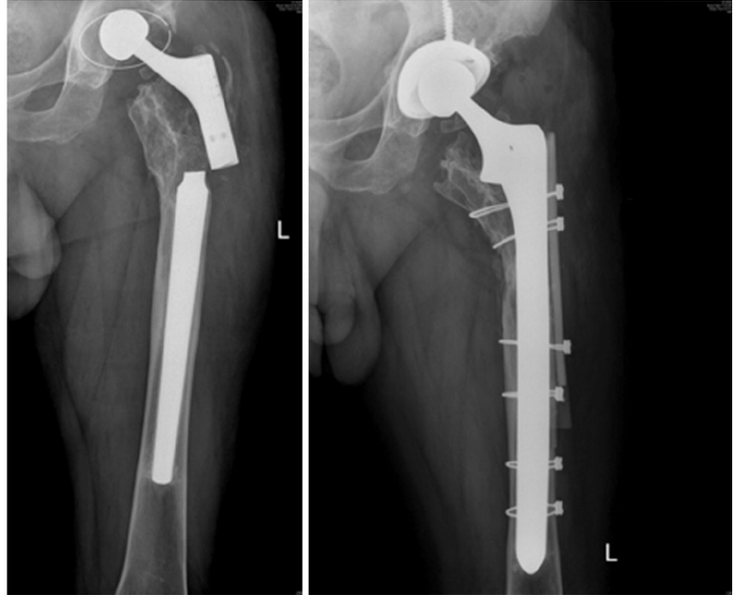

uomo di 64 anni portatore di due protesi ad entrambe le anche eseguite nel 2013 e nel 2015, mentre va in bicicletta in una strada di medio traffico viene tamponato da un furgone e riporta la frattura periprotesica diafisaria prossimale del femore sinistro (protesi eseguita nel 2015).

Il giorno 16 dicembre 2019 viene eseguito intervento chirurgico di Revisione, osteosintesi con placca ad uncino e sostituzione stelo, periodo post operatorio trascorso in maniera ottimale.